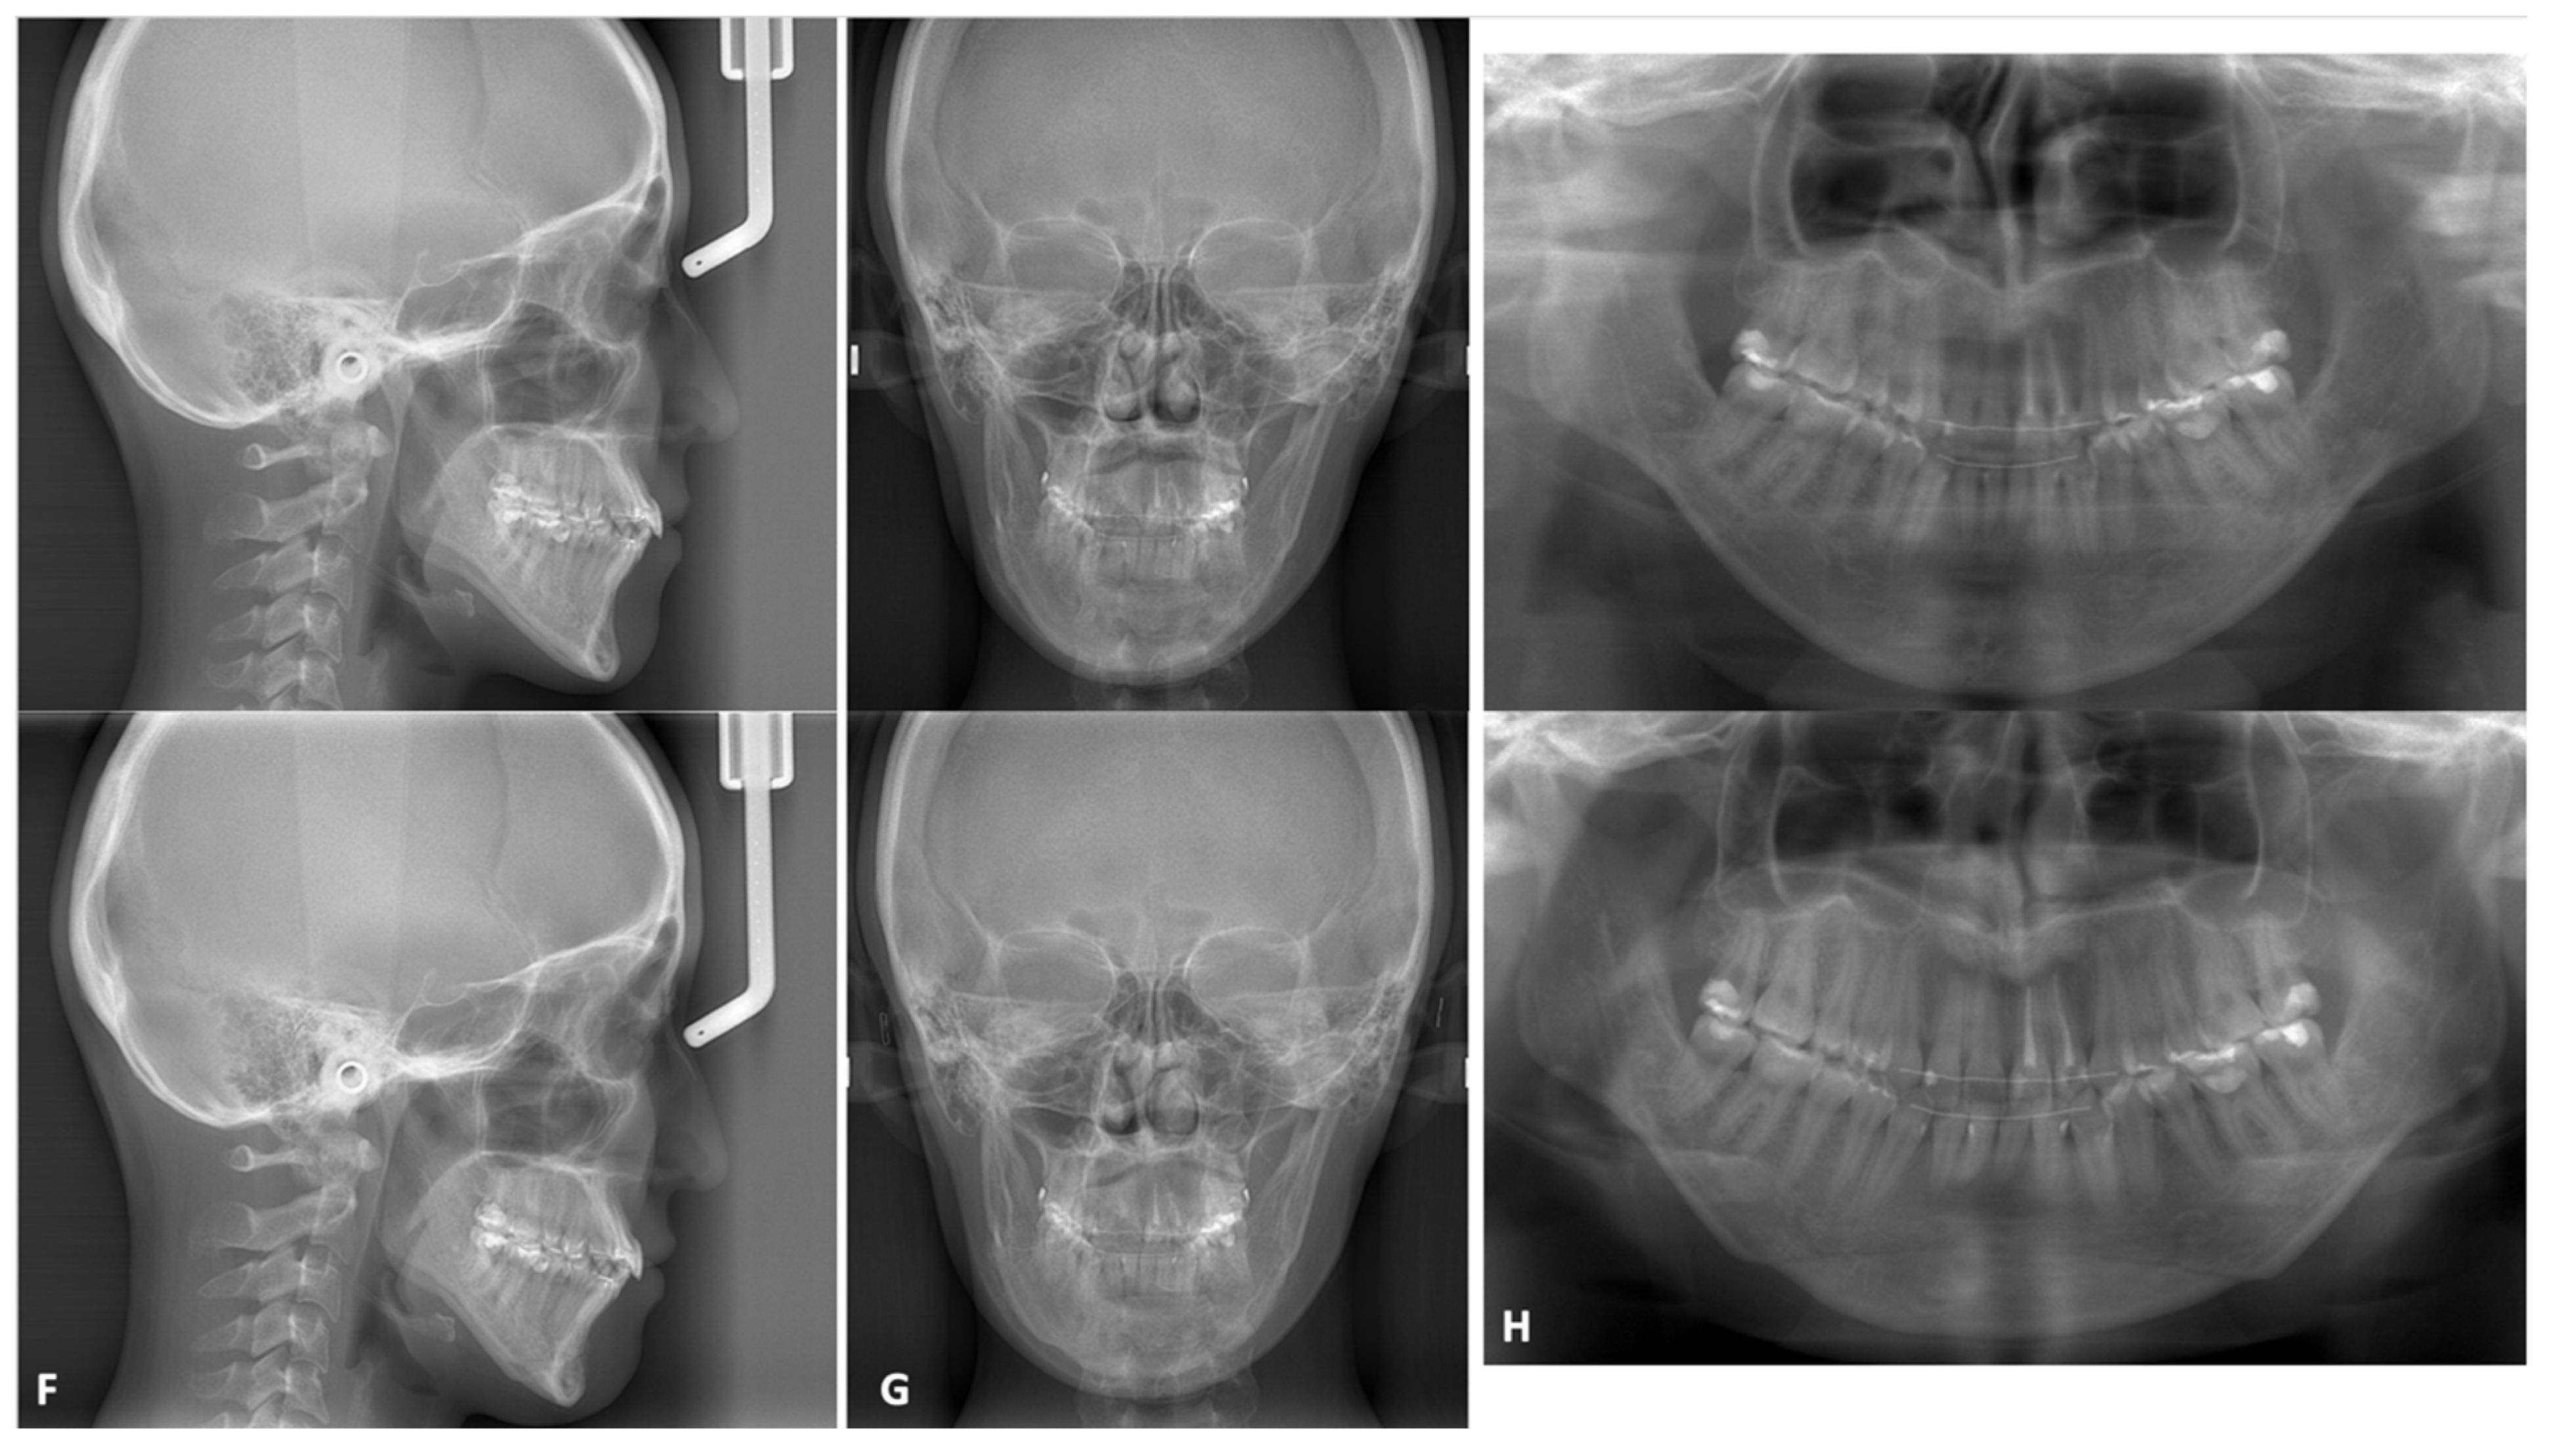

3.2.2. Mandibular Osteotomies

- Ueki, K.; Okabe, K.; Miyazaki, M.; Mukozawa, A.; Moroi, A.; Marukawa, K.; Nakagawa, K.; Yamamoto, E. Skeletal stability after mandibular setback surgery: Comparisons among unsintered hydroxyapatite/poly-L-lactic acid plate, poly-L-lactic acid plate, and titanium plate. J. Oral Maxillofac. Surg. 2011, 69, 1464–1468. [Google Scholar] [CrossRef] [PubMed] [Green Version]

- Ueki, K.; Okabe, K.; Marukawa, K.; Mukozawa, A.; Moroi, A.; Miyazaki, M.; Sotobori, M.; Ishihara, Y.; Yoshizawa, K.; Ooi, K. Skeletal stability after mandibular setback surgery: Comparison between the hybrid technique for fixation and the conventional plate fixation using an absorbable plate and screws. J. Cranio-Maxillofacial Surg. 2014, 42, 351–355. [Google Scholar] [CrossRef] [PubMed]

- Ueki, K.; Moroi, A.; Yoshizawa, K.; Hotta, A.; Tsutsui, T.; Fukaya, K.; Hiraide, R.; Takayama, A.; Tsunoda, T.; Saito, Y. Comparison of skeletal stability after sagittal split ramus osteotomy among mono-cortical plate fixation, bi-cortical plate fixation, and hybrid fixation using absorbable plates and screws. J. Cranio-Maxillofacial Surg. 2017, 45, 178–182. [Google Scholar] [CrossRef]

- Sukegawa, S.; Kanno, T.; Manabe, Y.; Matsumoto, K.; Sukegawa-Takahashi, Y.; Masui, M.; Furuki, Y. Biomechanical Loading Evaluation of Unsintered Hydroxyapatite/poly-l-lactide Plate System in Bilateral Sagittal Split Ramus Osteotomy. Materials 2017, 10, 764. [Google Scholar] [CrossRef] [Green Version]

- Park, Y.-W.; Kang, H.-S.; Lee, J.-H. Comparative study on long-term stability in mandibular sagittal split ramus osteotomy: Hydroxyapatite/poly-l-lactide mesh versus titanium miniplate. Maxillofac. Plast. Reconstr. Surg. 2019, 41, 8. [Google Scholar] [CrossRef] [PubMed] [Green Version]